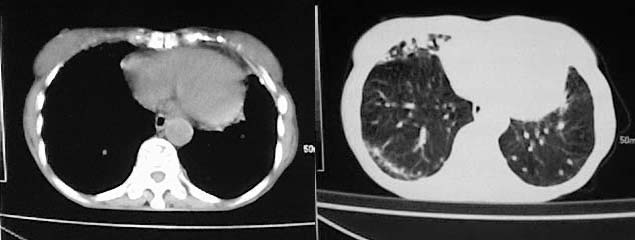

以下是引用有风的日子在2008-5-2 12:13:00的发言:[br][emb10][br][br]肺ca?有病理支持吗?[br][br]我看更象是肺tb并支扩、间质性肺炎。最好拿个病理结果来,不然这点影像资料诊断肺ca是难以服人的![br][br]至于主动脉瘤的诊断问题,国外认为≥4.0cm就可诊断了,国内对此诊断标准更为严格。患者升主动脉明显增粗,即>4cm。你诊断个升主动脉扩张并不为过!

以下是引用zjzjr在2008-5-2 14:39:00的发言:[br]支持双侧继发型肺结核,左侧胸膜肥厚,慢性支气管炎伴间质纤维化.